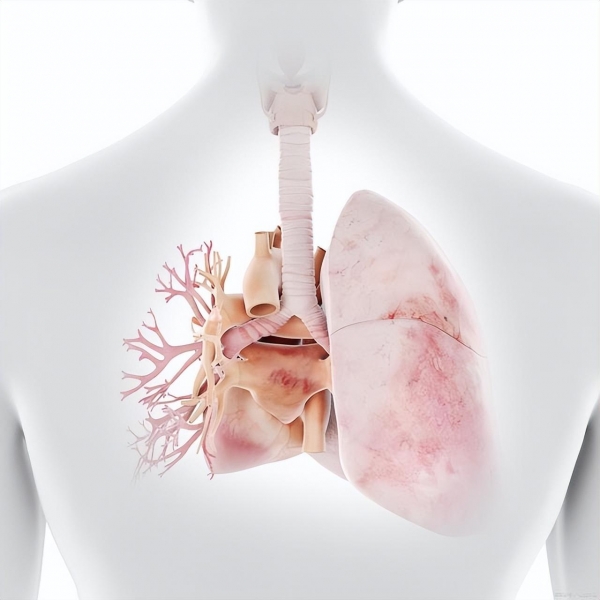

1. 原发性病毒性肺炎:流感病毒直接侵犯肺泡和气道,引起充血、水肿及炎症反应,这些改变可能在影像学检查中表现为肺实质的密度增加。

2. 继发性细菌性肺炎:流感会损伤上呼吸道的防护屏障,使患者更容易受到细菌的侵袭,从而发展为继发性细菌性肺炎。这类肺炎通常也会在X光片上显示为密度增高的区域。

3. 急性呼吸窘迫综合征 (ARDS):在严重的流感感染中,炎症反应可以变得非常剧烈,导致肺部损伤并引起ARDS,肺部广泛的炎症和液体渗漏进入肺泡,导致在影像上出现大片"白化"区域。

4. 肺水肿:由于流感引发的重症或合并心脏问题,可能导致肺泡毛细血管壁通透性增加,液体积聚于肺泡内,同样会在胸片上表现为肺部密度增加。

5. 免疫反应:强烈的免疫系统反应对流感病毒的攻击可能对肺组织造成"友火攻心"的伤害,称为细胞因子风暴,这可能导致肺部充血和水肿,在影像上显示为较白的区域。